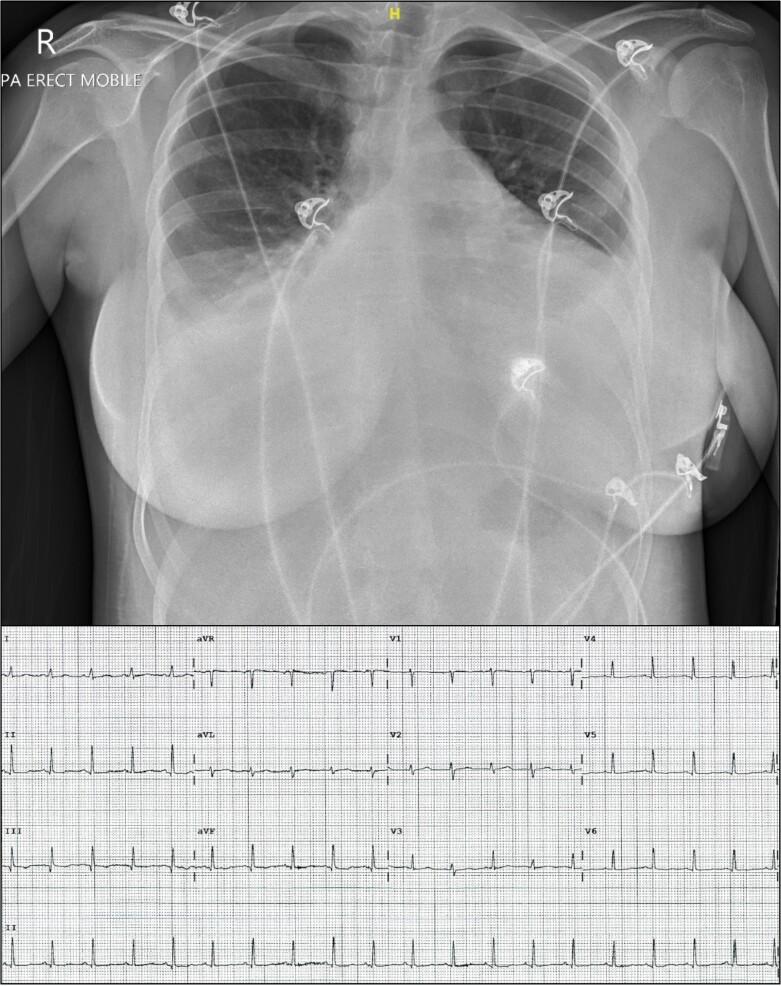

This series describes two cases of this syndrome which demonstrates acute right ventricular failure as a mechanism of PDS and provides insights into the echocardiographic findings and clinical course of this poorly understood syndrome. Case 1 describes a patient who underwent pericardiocentesis, whilst Case 2 describes a patient who underwent surgical pericardiostomy. In both patients, acute right ventricular failure was observed following the release of tamponade and is favoured to be the cause of haemodynamic instability.

Pericardial decompression syndrome is a poorly understood, likely underreported complication of pericardial drainage for cardiac tamponade associated with high morbidity and mortality. Whilst a number of hypotheses exist as to the aetiology of PDS, this case series supports haemodynamic compromise being secondary to left ventricular compression following acute right ventricular dilatation.